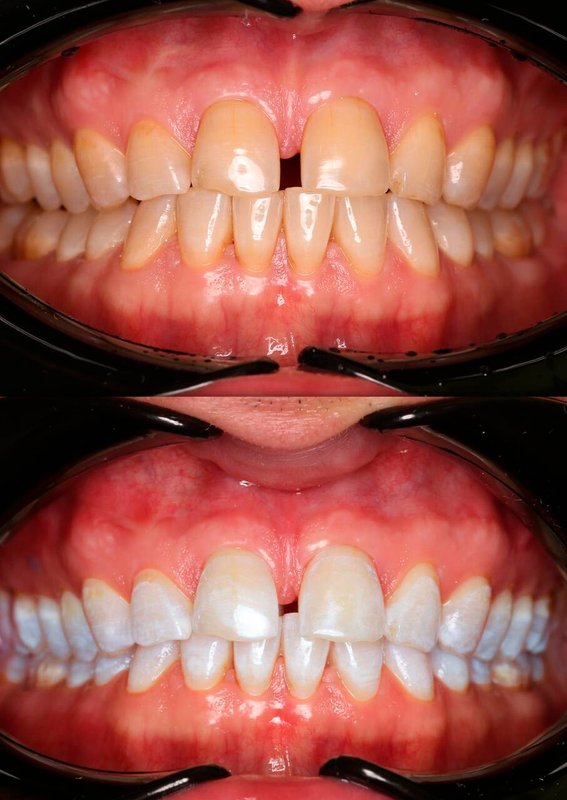

Фотогалерея

Если вы собираетесь добиться сияющей улыбки, то работу над ней лучше доверить экспертам. В стоматологической клинике Династия Н имеется специализированное оборудование для того, чтобы ваши зубы снова стали белоснежными. В нашей стоматологии оказывают услуги лечения кариеса, удаления зубов, компьютерной томографии, отбеливания, исправления прикуса, рентгенологической диагностики, изготовления имплантов, а также установки металлокерамики, брекетов, имплантов, виниров. С нами ваша улыбка будет яркой, а зубы крепкими!

Занимается эстетической реабилитацией улыбки путем отбеливания, художественной реставрацией и виниров, а также лечением таких заболеваний, как кариес, пульпит, периодонтит, гингивит, гиперестезия, флюороз и др.